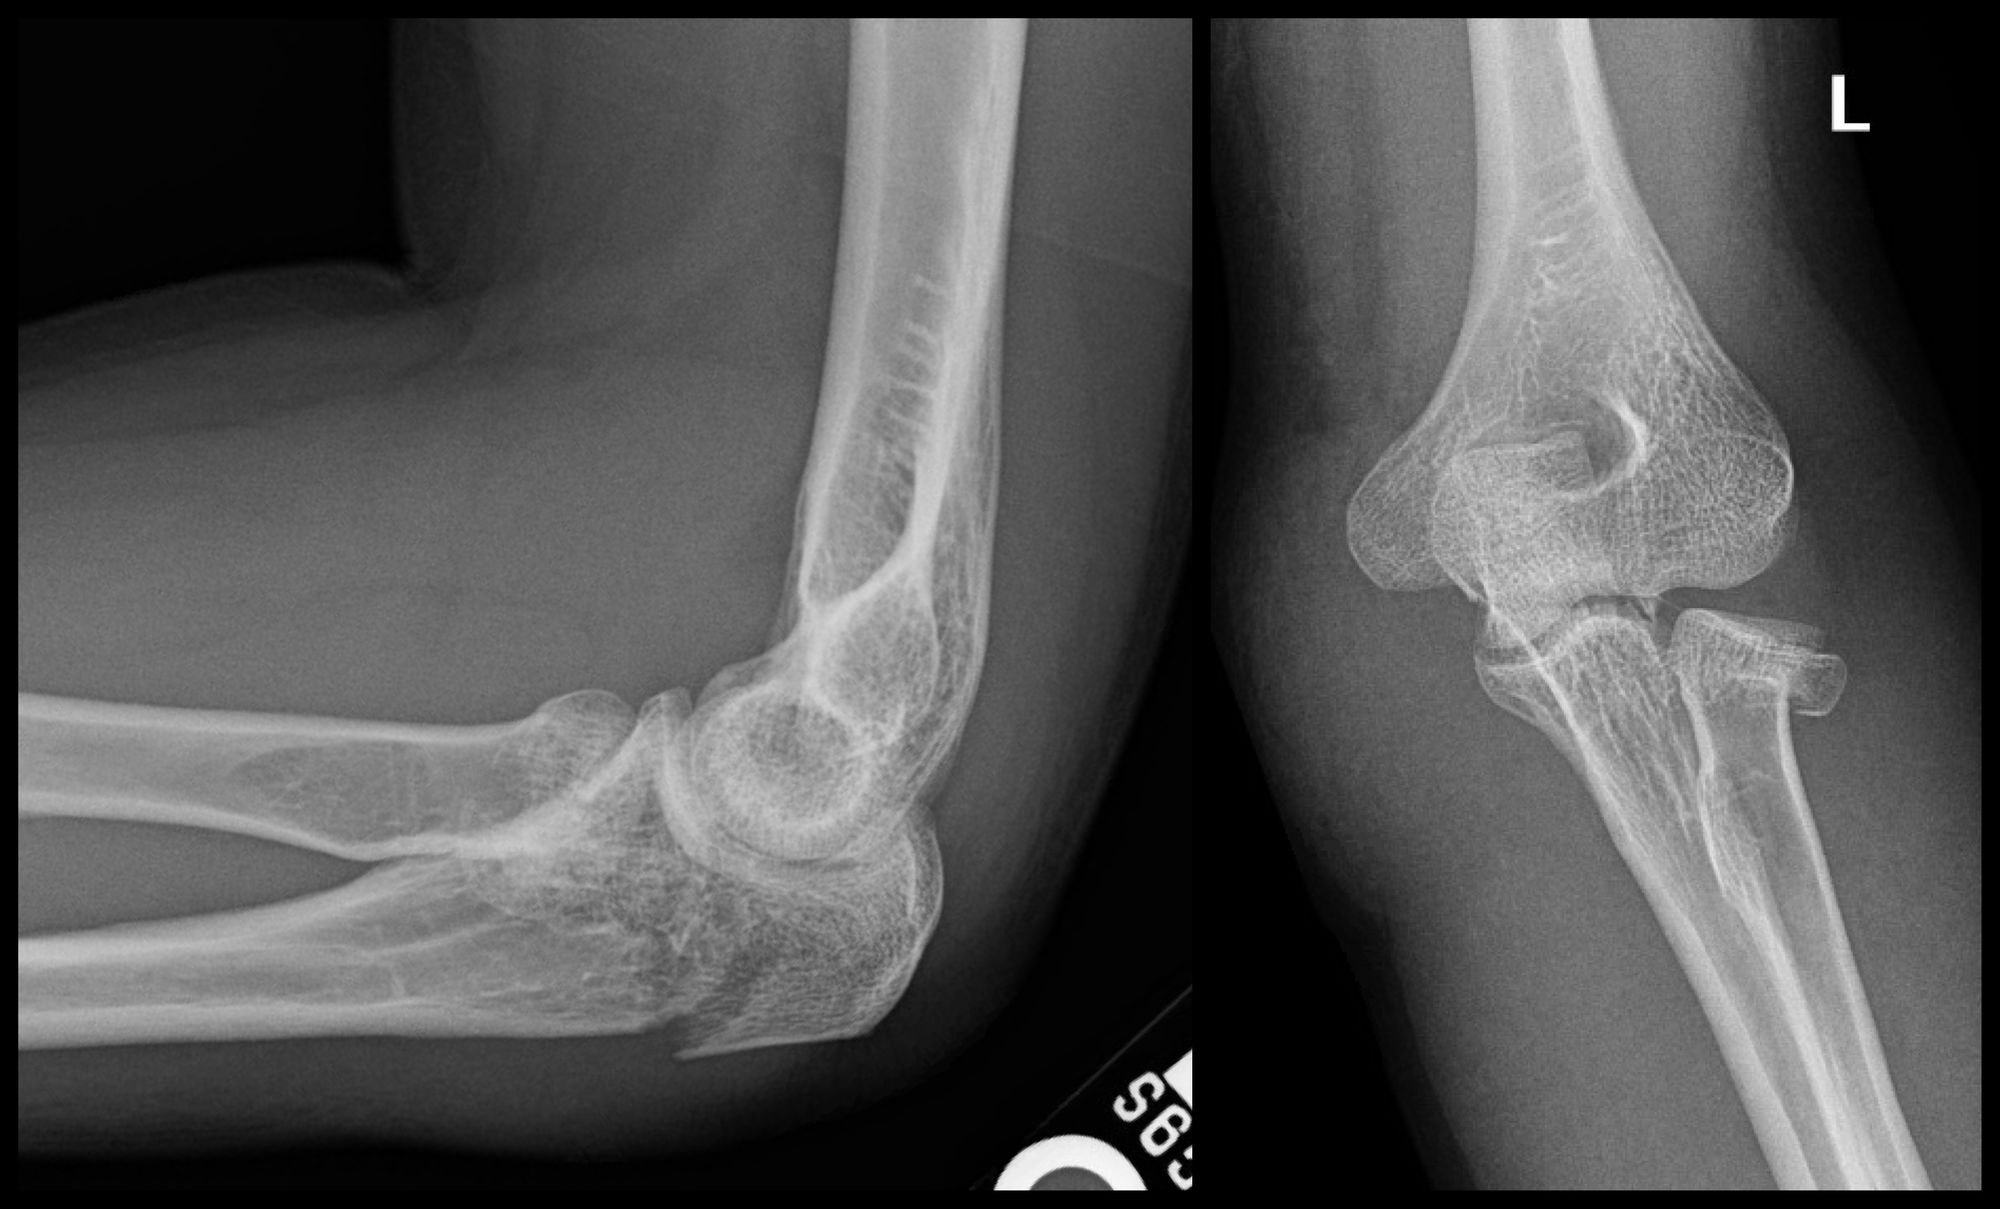

Olecranon and Radial Head ORIF